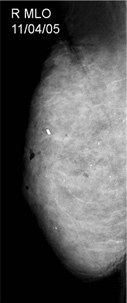

45 year old asymptomatic woman had a Screening Mammogram and was advised to return for Whole Breast Ultrasound Screening because of her breast density and maternal history of breast cancer at age 54.The mammogram shows marked fibrocystic change with multiple microcalcifications and cysts, but no suspicious findings. Whole Breast Ultrasound Screening showed numerous less than 1 cm cysts, and also an 11 mm suspicious, spiculated mass at 12:00 on the right.

The mammogram on the upper right shows extremely dense parenchyma with multiple calcifications scattered throughout, but no focal abnormality.